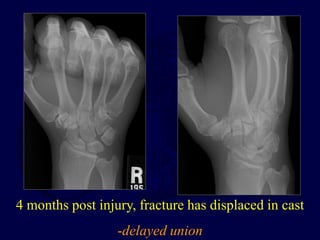

4 months post injury, fracture has displaced in cast

-delayed union

26 y/o male, injuredskiing; film at 10 days

4 months postinjury, fracture has displaced in cast -delayed union